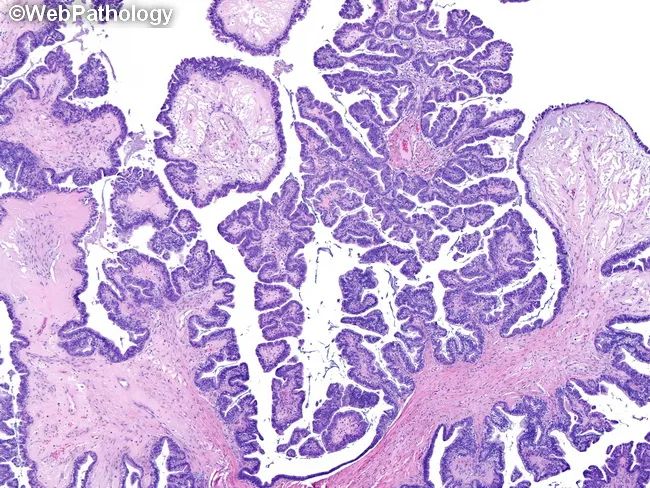

(结构)囊腔内结构复杂,>10%区域衬覆上皮增生(复层、出芽和乳头)[特征] 乳头由大到小、逐级分支,并可见单个细胞或细胞团游离在腔内[特征] 局灶可能出现出芽互相融合,形成罗马桥或筛状结构,局灶可能出现微乳头型成分,范围<5mm,缺乏不规则生长的实性区、密集小巢状或复杂腺样结构 (即缺乏间质浸润)

(细胞)细胞形态具有一定异质性,乳头常衬覆立方或柱状的输卵管型上皮 (纤毛细胞或分泌细胞)[特征] ,可伴有多少不等的多角形细胞或靴钉样细胞,胞浆嗜酸性,1/3肿瘤含有一些核圆形伴丰富嗜酸性胞质细胞,核染色质细腻,偶可见核仁,核异型性轻度,核分裂象少见 (<4个/10HPF),常可见砂粒体(超过一半的病例)